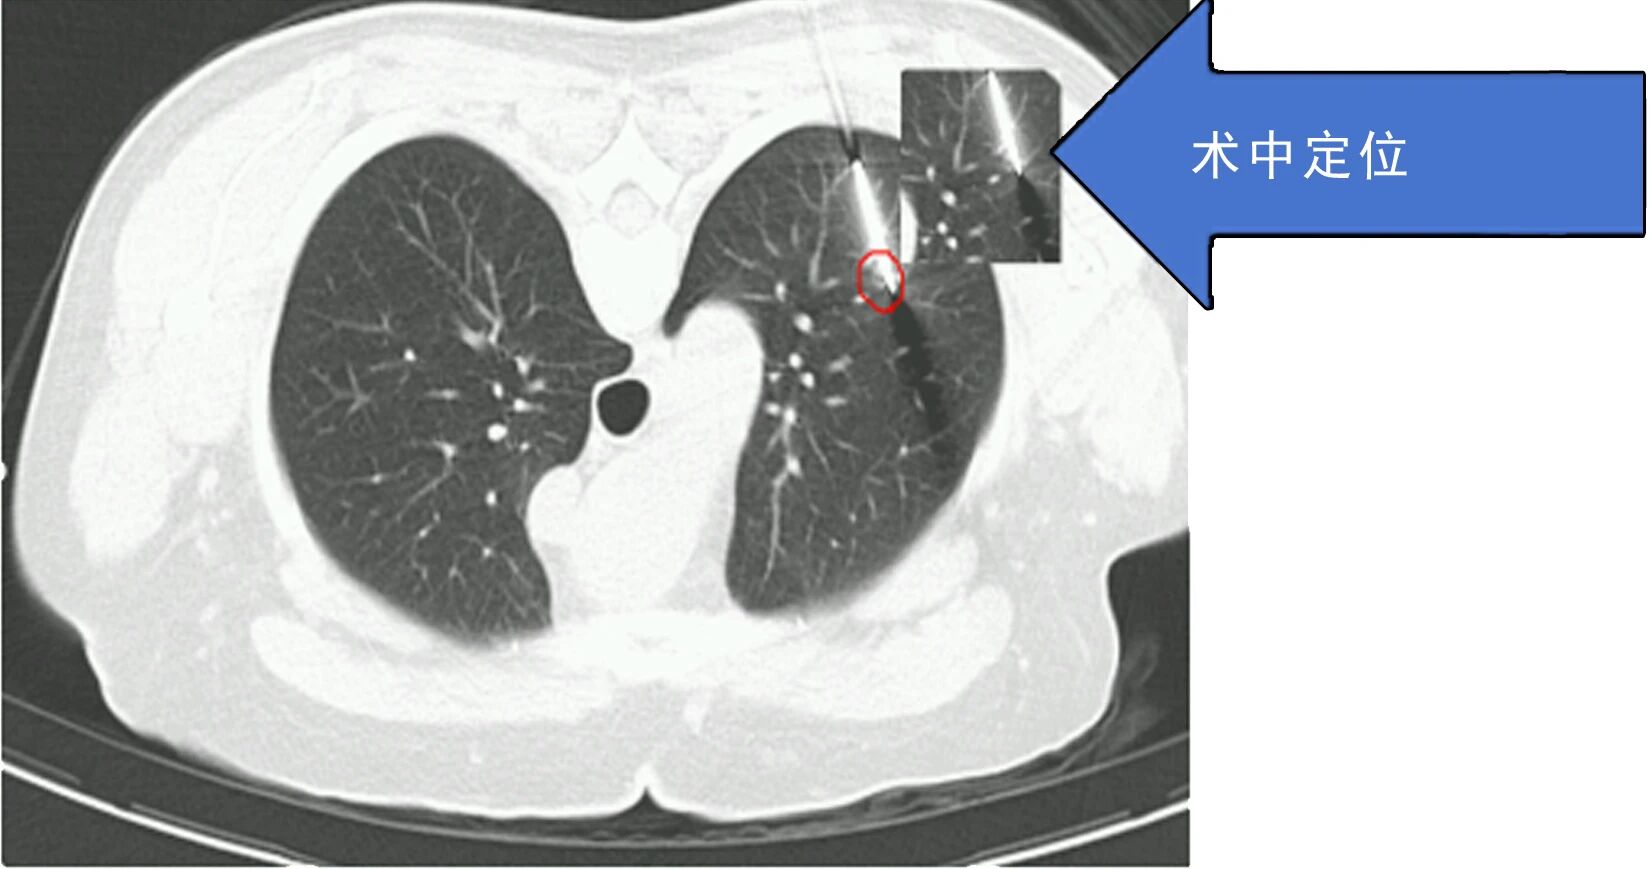

患者因肺结节就诊后,术前检查提示传统手术可能造成较大肺功能损伤,患者及家属因此产生明显焦虑情绪。胸外科团队综合评估病情后,决定采用微波消融技术施治。手术依托CT实时导航技术,将消融针精准送达结节部位,误差控制在3毫米以内,仅通过一个针孔创口完成操作,单次消融过程耗时5-10分钟,患者3天内出院,健康肺组织功能得以保留。